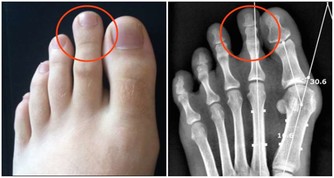

信號五:腳趾甲異常

△健康徵兆:

1、趾甲厚重發黃:可能由於黴菌感染而引起,糖尿病患者、有循環問題和免疫系統問題的人容易感染該疾病;

2、趾甲有凹痕:可能由於微量元素缺乏所引起,也有可能是其他疾病,

如牛皮癬關節炎,表現為指甲有很多小洞,可深可淺。

△解決對策:

①指甲真菌感染極其頑固,使用藥物也難以消除,建議在發現最初癥狀后馬上看醫生;

②如缺乏微量元素,可多吃一些含脂肪、碳水化合物(即澱粉、糖類等)較豐富的食物,

豆製品、蔬菜、瓜果等,如伴有其他疾病,應及時找專業醫生診治;

③如果厚指甲難以修剪,最好先在溫鹽水中浸泡10分鐘,然後用含有乳酸或尿素的乳液摩擦指甲。